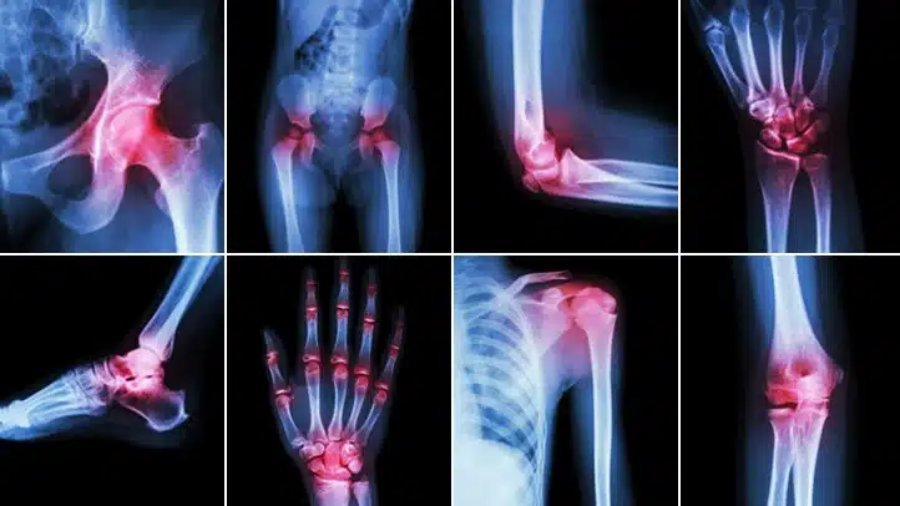

درمان قطعی قوز شست پا قوز شست پا (Hallux Valgus)، که به انحراف شست پا به سمت انگشتان دیگر اطلاق میشود، یکی از شایعترین و آزاردهندهترین عارضههای ارتوپدی است. این وضعیت، تنها یک مشکل ظاهری نیست، بلکه میتواند با درد، التهاب، و اختلال در راه رفتن همراه باشد و کیفیت زندگی افراد را به شدت […]